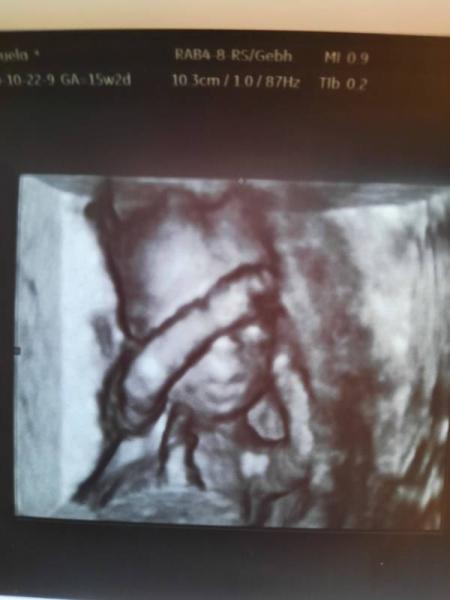

Hallo, komme gerade von der Ärztin und gsd ist alles ok und der Magen war sofort sichtbar Bin so erleichtert Wunderschöne Fotos habe ich auch bekommen aber nur leider eine Tendenz und kein sicheres outing. Aber das erste mal überhaupt das sie glaubt es ist ein Mädchen jetzt ist die spannung noch grösser jommt mir vor

Foto vergessen

Bild zu